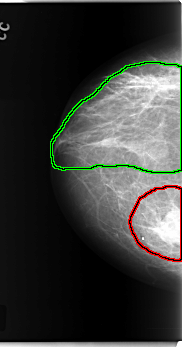

FILE: C_0189_1.RIGHT_MLO.OVERLAY

TOTAL_ABNORMALITIES 3

ABNORMALITY 1

LESION_TYPE CALCIFICATION TYPE PLEOMORPHIC DISTRIBUTION CLUSTERED

LESION_TYPE MASS SHAPE ROUND MARGINS CIRCUMSCRIBED

ASSESSMENT 5

SUBTLETY 5

PATHOLOGY MALIGNANT

TOTAL_OUTLINES 1

ABNORMALITY 2

LESION_TYPE CALCIFICATION TYPE PLEOMORPHIC DISTRIBUTION REGIONAL

ABNORMALITY 3

BOUNDARY